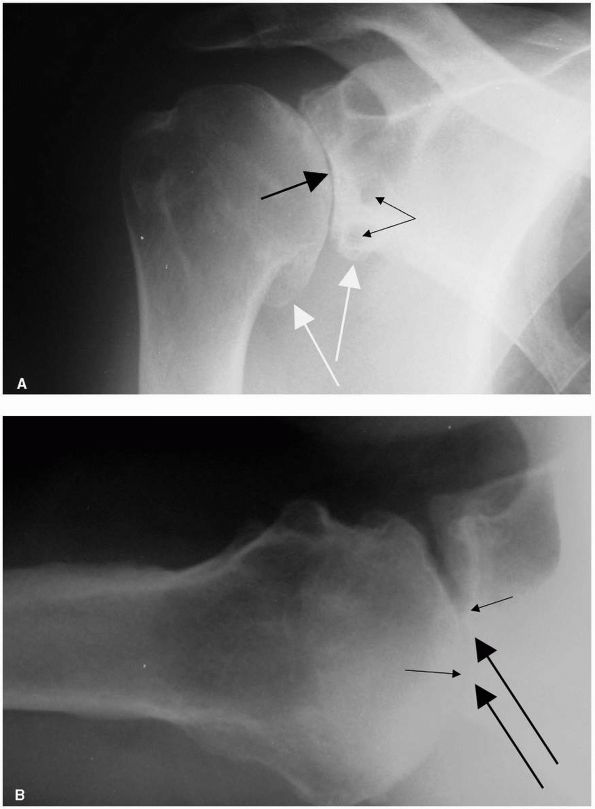

![]() |

FIGURE 12-7. Glenohumeral osteoarthritis. (A) Anteroposterior radiograph demonstrating joint space narrowing (large black arrow), osteophyte formation (large white arrows), and subchondral cysts (small black arrows). (B) Axillary view showing typical posterior glenoid wear (large black arrows)

and posterior subluxation of the humeral head. The small black arrows indicate normal points of contact between the head and the glenoid. |